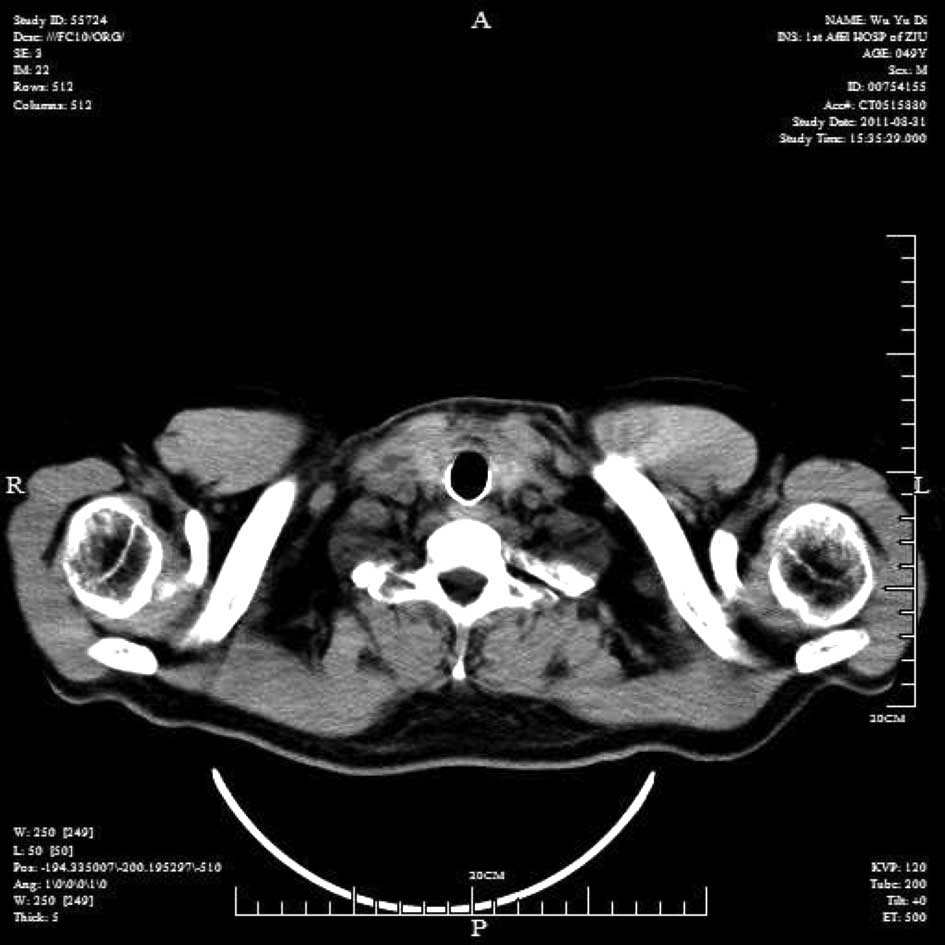

Emergency management of a patient with severe airway obstruction resulting from poorly differentiated thyroid carcinoma: A case report

We present a case of a life-threatening almost complete airway obstruction resulting from poorly differentiated thyroid carcinoma in a 48-year-old male. Airway obstruction may lead to unexpected mortality by suffocation and patients with poorly differentiated thyroid carcinoma usually have a fast deterioration and fatal outcome. In the case presented, we describe a safe and effective treatment strategy. Assisted by femoro-femoral cardiopulmonary bypass oxygenation, a tracheal stent was implanted successfully. Following surgery there were no complications, and chemoradiotherapy resulted in the relief of obstructing symptoms and improved the quality of life of the patient. This case indicates that femoro‑femoral cardiopulmonary bypass provides adequate oxygen support to undergo further management and that tracheal stent implant is an effective emergent measure to relieve severe airway obstruction in patients with poorly differentiated thyroid carcinoma.

Figure 1

Figure 2

Figure 3

Figure 4

Figure 5

Figure 6